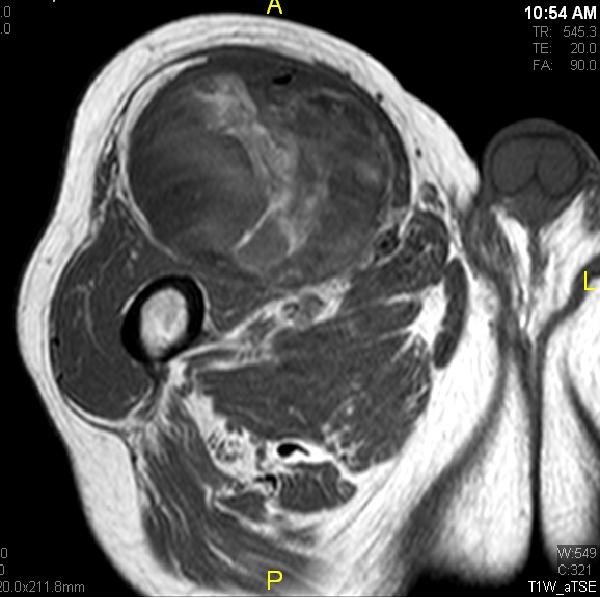

Fig. 1 & 2 Magnetic Resonance Image shows a large heterogeneous mass in the left gluteal region with low intensity signal on Axial (Fig. 1) and Coronal (Fig. 2) T1-weighted images admixed with some high signal areas indicative of fatty tissue. Higher intensity signal is visible compatible with hemorrhage or necrotic tissue. The mass involve the central portion of the left iliac bone.

Fig. 3 Axial fat suppressed T2-weighted MR image demonstrates a large heterogeneous mass with multiple thick internal trabeculations. Fatty areas suppress on T2 weighted fat suppressed areas

• Large encapsulated lipomatous mass with multiple thick internal trabeculations. (Fig. 1 – 13)

• High signal intensity both on T1-weighted and T2 weighted (Fig. 3)

• Signal loss on FS T1 weighted images, and focal nodules(>1 cm is suggestive of a DDLS). (Fig. 1 & 7)

• Low intensity images are visible in case of Hemorrhage.

• Contrasted images show hyper-enhancement of the tumors. (Fig. 4, 5, 11-13)